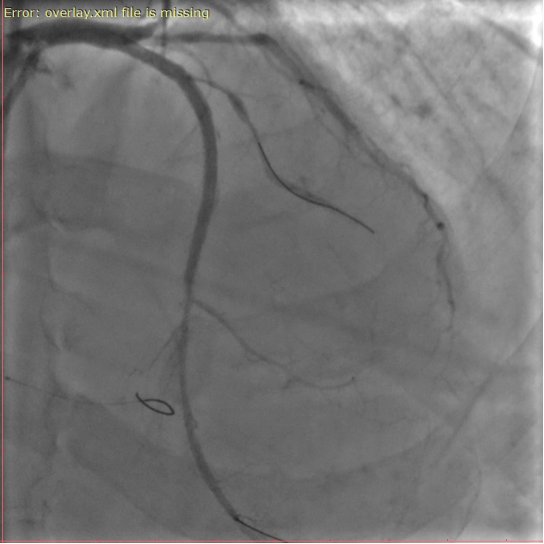

患者为62岁男性,此次入院前反复胸痛,伴有一次心源性晕厥的发生,就诊我院完善冠脉造影示前降支血管近段完全闭塞,为CTO病变,其余两支冠脉血管均有重度狭窄,因病变复杂且风险极高,建议家属首选外科搭桥手术,但经过反复沟通后患者及家属希望尝试微创介入治疗。

手术中,郭旭主任与团队成员密切协作,经过3个小时的不懈努力,在正向导丝技术通过失败的情况下,灵活更换多种治疗策略,最终通过更具挑战性的逆向CTO-PCI技术经侧支循环精准通过闭塞段,成功开通左前降支闭塞病变,全程操作流畅,术后患者无并发症,症状显著缓解。

△术前、术中、术后